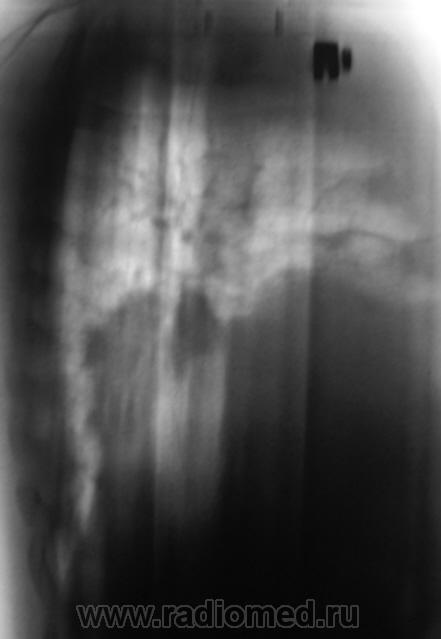

Пациент, после анализа флюорограмм "взят на контроль". Произведено стандартное дообследование - рентгенография в прямой и правой боковой проекциях, боковая томография. По большому счету, пациет жалоб не предъявляет.

Вначале думал о центральном раке, ателектазе, но на томограммах видно четко бронхи "воздушная бронхограмма". Может пневмония?.

Массивное затемнение "вне анатомических границ", рождает сомнения по поводу "осумкования". Что за снижение прозрачности "сзади", но фоне чего хорошо дифференцируется бронх - думаю, что "инфильтрация". пациент в стационаре, назначена противовоспалительная терапия. По всей видимости, динамика будет выставлена, если "область не заберет на себя".

Мыслей о междолевом осумкованном плеврите нет, т.к. контуры не ровные, о центральном раке не думаю т.к. бронхи говорят об их интактности, думаю пока о пневмонии. Динамика в данном случае, в паре с лечением должа дать ответ.

Кроме того, у меня впечатление о наличии полостного образования в S3 в/доли